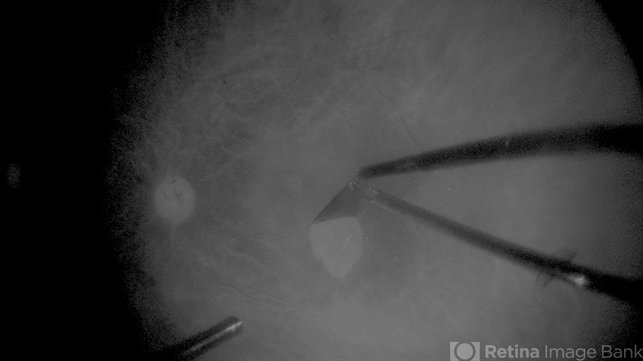

- Macular surgery, monochrome, enhaced contrast

- Nassim Abreu, Hospital Dr. Elías Santana

- NGenuity 3D system

- Frame grab from a 68 year male, who underwent cataract surgery and vitrectomy with ilm peel because of PDR. In the picture we can see the enhanced contrast we can get while doing an ILM peel with a monochromatic digital filter